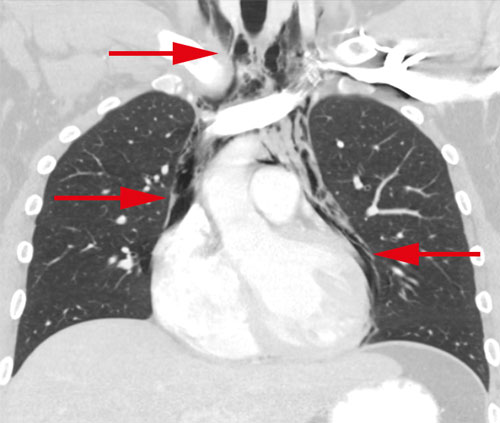

En översiktlig ultraljudsundersökning av hjärtat gjordes bedside för att se eventuell perikardvätska. Patientens hjärta var svårundersökt med ultraljud och kunde inte visualiseras i sin helhet, vilket är ovanligt hos en yngre normalbyggd man. Någon tydlig perikardvätska kunde dock inte påvisas. Blodprov visade normala värden för troponin T, CRP och LPK. För att utesluta pneumotorax gjordes lungröntgen som visade en luftspalt i mediastinum och kring hjärtat, fynd som vid pneumomediastinum och pneumoperikardium (Figur 1). I syfte att utesluta framför allt esofagusruptur som orsak till pneumomediastinum undersöktes patienten med datortomografi av torax med intravenös och peroral kontrast. Även denna undersökning visade luft i mediastinum och perikardiet. Inga tecken till kontrastläckage från esofagus eller andra patologier kunde påvisas (Figur 2–4). Luften kring hjärtat bedömdes förklara svårigheten att undersöka hjärtat med ultraljud. Mot bakgrund av anamnes och radiologiska fynd ställdes diagnosen spontan pneumomedia­stinum och pneumoperikardium. Ingen ytterligare akut utredning bedömdes nödvändig. Han överflyttades till toraxkliniken vid Karolinska universitetssjukhuset för fortsatt observation och smärtlindring. Han förbättrades snabbt och skrevs ut 3 dagar senare, och vid telefonuppföljning efter en månad var patienten helt återställd.

Figur 2. Datortomografi av torax med intravenös kontrast samt peroral kontrast visar strimmor av luft i halsens mjukdelar (övre pilen), i mediastinum (mellersta pilen) samt i perikardiet (nedersta pilen åt höger). Peroral kontrast kan på bilden ses i magsäcken.